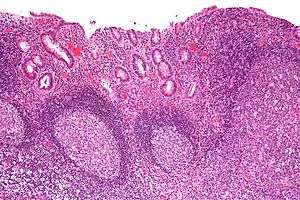

| Micrograph showing colonic-type mucosa with follicular lymphoid hyperplasia, as is seen in diversion colitis. H&E stain. | |

Diversion colitis is an inflammation of the colon which can occur as a complication of ileostomy or colostomy, often occurring within the year following the surgery. It also occurs frequently in a neovagina created by colovaginoplasty, with varying delay after the original procedure.[1] Despite the presence of a variable degree of inflammation the most suggestive histological feature remains the prominent lymphoid aggregates. A foul smelling, mucous rectal discharge may develop from the inflamed mucosa of the distal, unused colon.